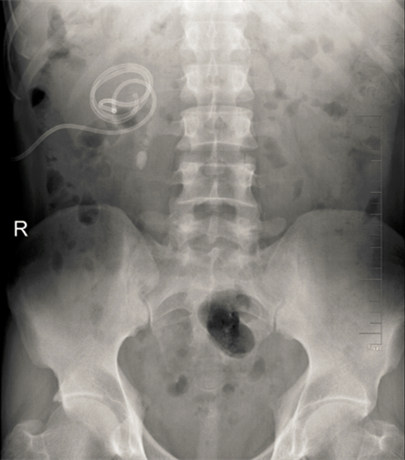

术后KUB见双肾造瘘管,及双侧内支架管固定妥善

正常人输尿管长约25cm左右,该患者输尿管迂曲扩张,长达35-40cm左右,裁剪部分输尿管成型